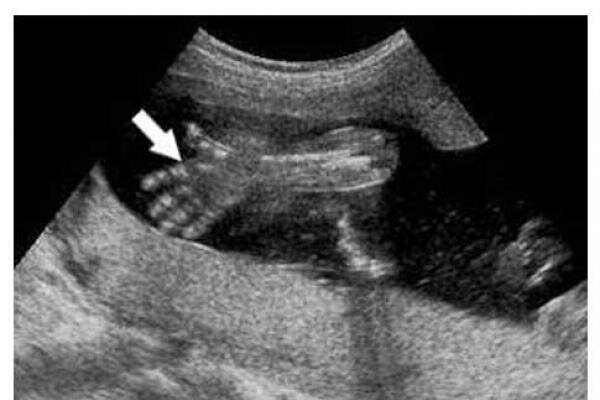

دکتر صغری ربیعی در گفتوگو با ایسنا اظهار کرد: انجام غربالگری با هدف اطمینان از سلامت جنین و پرورش جامعهای سالم انجام میشود که حذف اجباری بودن غربالگری در آینده تنها افزایش جمعیت معلول را به دنبال دارد چراکه با حذف غربالگری هیچ اطلاعاتی از وضعیت جنین نخواهیم داشت.

وی با بیان اینکه موضوع غربالگری دوران بارداری در جامعه به موضوعی جا افتاده تبدیل شده، تصریح کرد: بسیاری از زنان باردار در دوران بارداری به دنبال انجام تست غربالگری هستند و این موضوع نشان میدهد جامعه موضوع غربالگری را پذیرفته است بنابراین حذف اجباری بودن طرح غربالگری جامعه معلول را افزایش میدهد.

دکتر ربیعی با بیان اینکه هنگام متوجه شدن از وضعیت جنین در صورتی که جنین ناقص باشد دوران بارداری متوقف میشود، تصریح کرد: انجام تست غربالگری نوعی سرمایه گذاری برای داشتن آرامش در خانواده است چراکه در صورت تولد فرزند معلول خانواده تا پایان عمر درگیر و بر دوش خانواده و حتی جامعه هزینه تحمیل میشود.